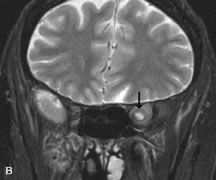

Extraocular muscle enlargement in patients with thyroid-associated orbitopathy is demonstrated equally well with CT and MRI studies. However, the superior tissue contrast on MR images reveals better details of the relationships of the optic nerve to the thickened muscles at the orbital apex (Fig. 16).50 In addition, MRI may be able to differentiate between muscles that are enlarged as a result of edema and active inflammation and those enlarged because of fibrosis by their T2 relaxation times.21 Quantitative MRI was not found to be accurate in predicting the success of low-dose orbital irradiation.51 However, a muscular index relating the diameters of the rectus muscles to the bony orbital dimensions was useful in predicting optic nerve compression.52

Fig. 16. A-C, T1-weighted MR scans obtained with a high-resolution surface coil demonstrate fusiform enlargement of the extraocular muscles. The medial, lateral, and inferior rectus muscles are especially involved. Note the relative sparing of the tendinous insertions, a finding characteristic of this disease process, as well as fatty infiltration of the lateral and inferior rectus muscles. There is marked proptosis, best visualized on the sagittal image (A), and mild crowding of the optic nerve at the orbital apex.